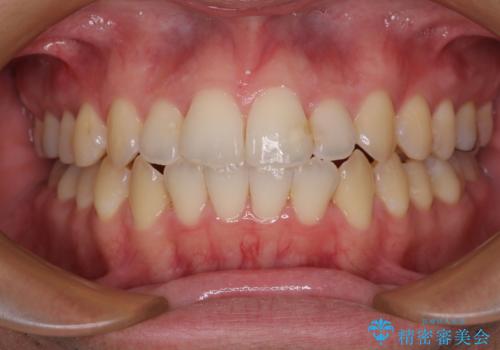

開咬とデコボコを整える インビザライン矯正治療

- 前歯の開咬と叢生を気にして来院された患者様です。

開咬の治療は、前歯を閉じるように動かすとともに、上下臼歯を圧下(骨内にめり込ませる)させることで進めて行きます。

オープンバイトは舌の突出癖により誘発され、治療後も突出癖が残っている容易に後戻りしてしまいます。

治療期間を短縮するためにも、舌突出癖の改善が極めて重要となります。